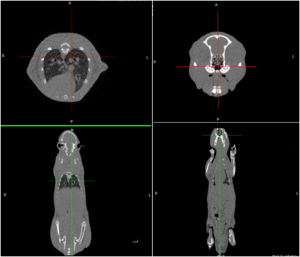

Super Nova系统扫描实验鼠CT图像

Super Nova系统扫描实验鼠PET、CT以及PET/CT融合图像